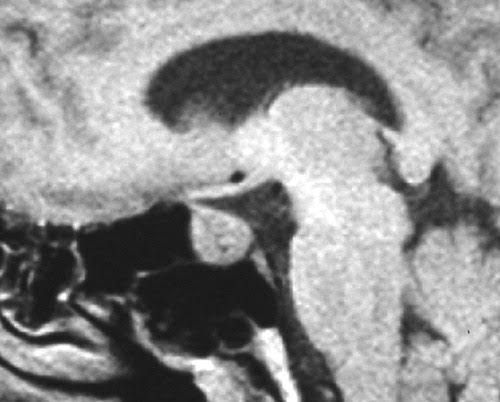

Wermer syndrome

A rare, inherited disorder that affects the endocrine glands and can cause tumors in the parathyroid and pituitary glands and the pancreas. These tumors are usually benign (not cancer).